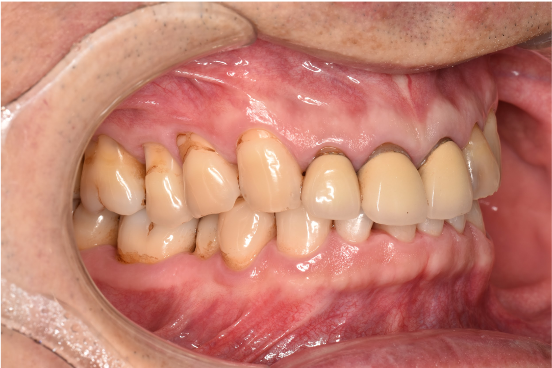

治療前

| カウンセリング・診断結果 | ご相談通り、全体的に着色と歯石が付着していました。歯周病の検査を行ったところ全体的に歯周病が進行しており、中等度~重度の歯周炎が認められました。 |

| 行ったご提案・治療内容 | 初診時に撮影したレントゲン、口腔内写真、歯周検査の結果を用いて、着色除去、歯周病治療の必要性をお伝えしました。 初診時は歯ブラシのお話しをさせていただき、セルフケアの方法について説明を行い、その後気にされてみえた着色除去、歯肉縁上歯石除去を行いましました。 歯肉の炎症がある程度落ち着いたところで、後日、再評価を行い歯周治療へ移行しました。 |